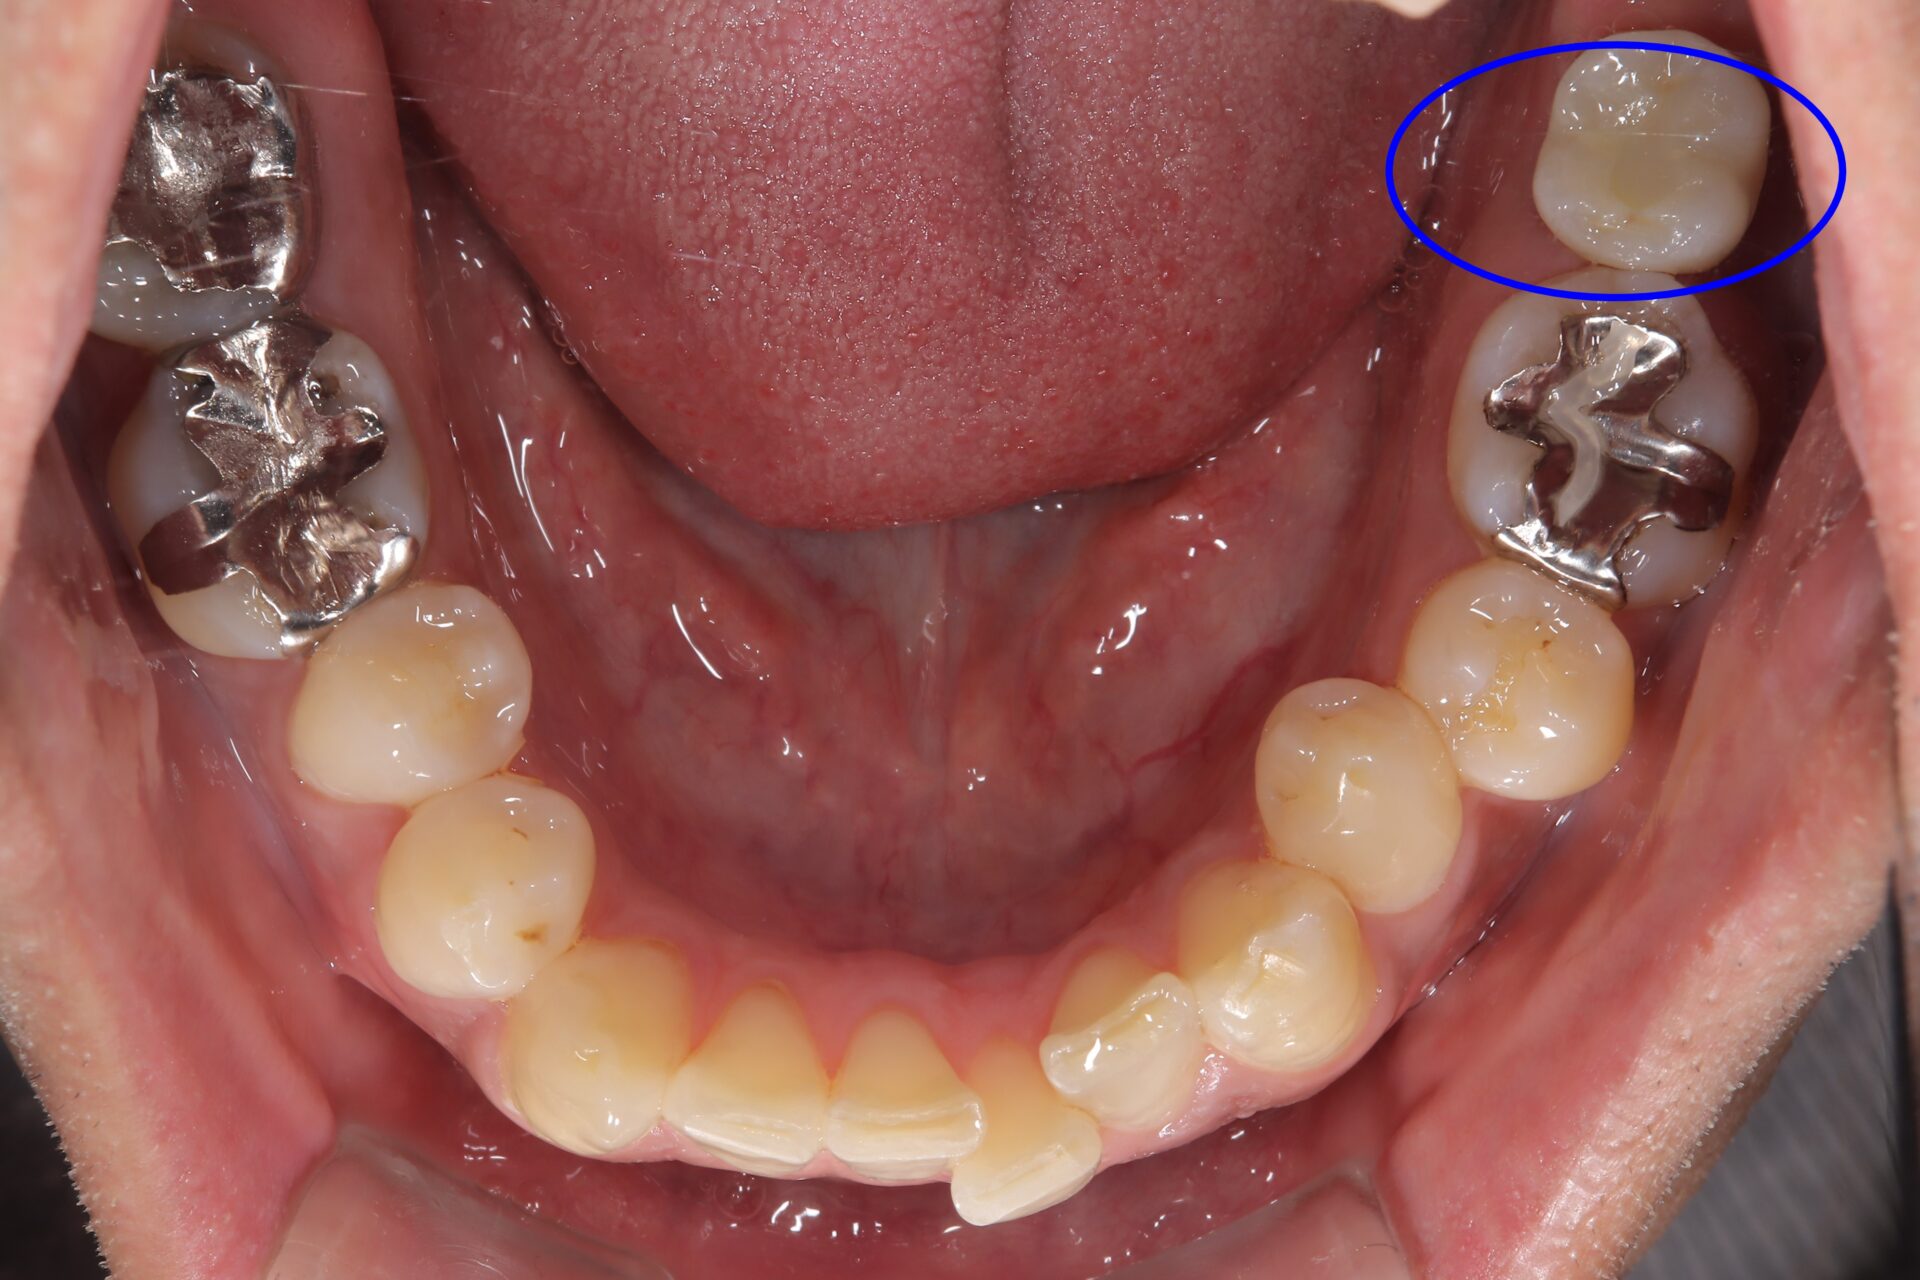

40代 女性

左上5番が歯根破折を起こし保存不可能な状態でした。

抜歯して3か月経過し骨の状態も問題のないことをCTで確認を行いました。

手術から3か月後に無事に被せ物まではいりました。かみ合わせも問題なく調子よく経過し現在術後2年経過しておりますが問題ありません。

左上の青い線で囲んであるとことが新しい歯になります。

経過も問題なくなんでも噛むことができるようになりました。

費用 | 45万円 |

治療期間 | 6か月 |